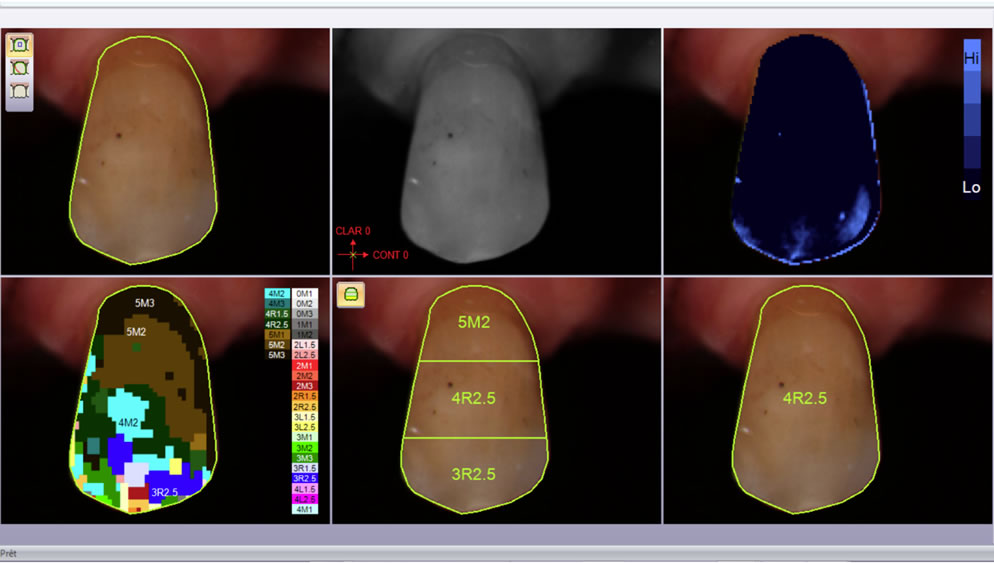

Le spectrophotomètre émet une lumière blanche calibrée (couvrant l’intégral du spectre des couleurs et non trivariante comme le colorimètre), le signal réémis est recapté et permet de définir la couleur de la dent. En fonction des systèmes, nous aurons des valeurs de teintiers (1 à 3 zones), voire même une cartographie très détaillée pour le prothésiste.

La société 3shape propose aujourd’hui de coupler l’acquisition du fichier 3D avec les données spectrophotométriques. L’avantage est d’envoyer au prothésiste dans un seul fichier l’ensemble des données permettant de réaliser une prothèse numérique. Cette technique nécessite une calibration spécifique du scanner intraoral ainsi qu’un enregistrement plus spécifique des zones de référence pour la couleur. Les zones insuffisamment enregistrées apparaîtront en bleu et le logiciel indiquera les zones de couleurs en références Vita Classic et 3D master.